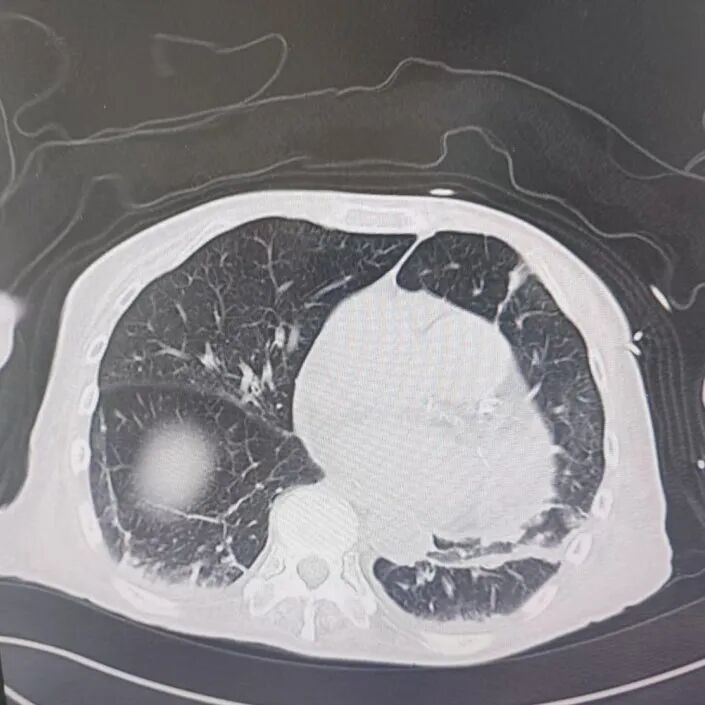

引言 / / Introduction 年近8旬的陳阿姨(化名)因腦梗長(zhǎng)期癱瘓?jiān)诖?,康?fù)期間突然高燒不退,體溫升至39℃,在抗感染過(guò)程中,她并發(fā)高滲性脫水,病情急劇惡化,被緊急送入ICU。此時(shí),她已氣管切開(kāi),依靠呼吸機(jī)維持呼吸,并伴有低蛋白血癥、低鉀高鈉血癥及房顫等多種危重情況,命懸一線! PART. 01 多重泛耐藥菌疊加大量基礎(chǔ)病 治療陷入“死胡同” 呼吸與危重癥醫(yī)學(xué)科及ICU通力協(xié)作,穩(wěn)住患者生命體征。治療過(guò)程中,進(jìn)一步的病原學(xué)檢查結(jié)果令人心驚:陳阿姨的肺部遭遇多種“超級(jí)細(xì)菌”混合侵襲,包括銅綠假單胞菌、鮑曼不動(dòng)桿菌、嗜麥芽窄食單胞菌、金黃色葡萄球菌、木糖氧化無(wú)色桿菌、粘質(zhì)沙雷菌等高度耐藥菌,堪稱(chēng)耐藥菌“大本營(yíng)”。這些細(xì)菌對(duì)常用抗生素幾乎全部耐藥,治療難度高,死亡率高。 治療前患者肺部影像 PART. 02 多學(xué)科強(qiáng)強(qiáng)聯(lián)手 量身定制攻堅(jiān)方案 面對(duì)無(wú)藥可用的困境,呼吸科沒(méi)有放棄!宋剛主任帶領(lǐng)團(tuán)隊(duì)聯(lián)合藥學(xué)部、檢驗(yàn)科、重癥醫(yī)學(xué)科成立多學(xué)科治療組,根據(jù)患者身體情況實(shí)時(shí)調(diào)整用藥,逐一攻破耐藥菌。這場(chǎng)與“超級(jí)細(xì)菌”的拉鋸戰(zhàn)持續(xù)了30多個(gè)日夜。 在醫(yī)護(hù)日夜堅(jiān)守和家屬全力配合下,陳阿姨的感染終于被遏制:高燒退了,肺部陰影消散了!就在即將宣告勝利時(shí),又發(fā)現(xiàn)她存在泌尿感染問(wèn)題,隨即轉(zhuǎn)入泌尿外科協(xié)同治療。當(dāng)宋主任回訪時(shí),看到陳阿姨精神煥發(fā)、體溫平穩(wěn),所有參與救治的人都感慨萬(wàn)分!這場(chǎng)救治,正是呼吸與危重癥醫(yī)學(xué)科攻堅(jiān)耐藥菌硬實(shí)力的生動(dòng)體現(xiàn)! 治療后患者肺部影像 從“無(wú)藥可用”到“絕處逢生”,此次成功救治,集中體現(xiàn)了呼吸與危重癥醫(yī)學(xué)科以耐藥菌精準(zhǔn)診治為核心的學(xué)科特色與技術(shù)優(yōu)勢(shì)。面對(duì)一次次的嚴(yán)峻挑戰(zhàn),科室始終秉持“生命至上、知難而進(jìn)”的信念,以多學(xué)科協(xié)作為平臺(tái),憑借個(gè)體化精準(zhǔn)用藥策略,為患者尋找生機(jī),為更多陷入困境的患者和家庭帶去了實(shí)實(shí)在在的希望。 PART. 03 人民醫(yī)院 人民名醫(yī) 宋剛 主任醫(yī)師 ·葫蘆島市第二人民醫(yī)院呼吸與危重癥醫(yī)學(xué)科主任 ·遼寧省生命科學(xué)學(xué)會(huì)東北呼吸與危重癥醫(yī)學(xué)(PCCM)分會(huì)遼寧省基層委員會(huì)副主任委員 ·遼寧省細(xì)胞生物學(xué)學(xué)會(huì)放射粒子治療專(zhuān)業(yè)委員會(huì)理事 ·遼寧省抗擊新冠肺炎疫情先進(jìn)個(gè)人 ·葫蘆島市勞動(dòng)鑒定委員會(huì)專(zhuān)家?guī)斐蓡T ·葫蘆島市醫(yī)學(xué)會(huì)呼吸內(nèi)科學(xué)分會(huì)第三屆委員會(huì)副主任委員 專(zhuān)業(yè)特色:擅長(zhǎng)呼吸系統(tǒng)疑難及急危重患者的救治,如急慢性支氣管炎、支氣管哮喘、慢性阻塞性肺疾病、肺炎、肺栓塞、肺癌、間質(zhì)性肺疾病、睡眠呼吸暫停綜合征等,尤其擅長(zhǎng)有創(chuàng)無(wú)創(chuàng)機(jī)械通氣、支氣管鏡下相關(guān)檢查及治療(TBNA、氣道支架置入術(shù)、球囊擴(kuò)張等)、全肺灌洗術(shù)等領(lǐng)先技術(shù),發(fā)表國(guó)家級(jí)期刊多篇。